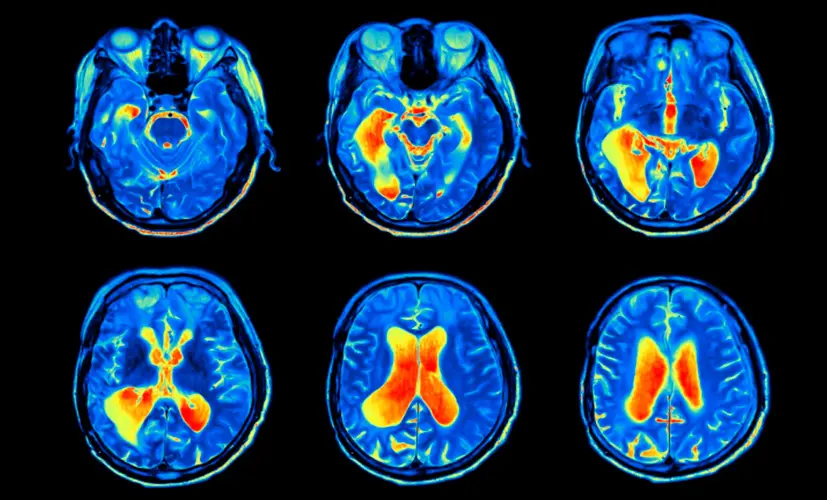

1.Complete memory loss - a life without clarity

The neural pathways in the brain become so damaged that no supplement can help. The person permanently loses their ability to recall memories. Relationships deteriorate. Confidence shatters. Depression takes hold. I've seen patients who isolated themselves at home, unable to face their loved ones.

2. Dementia - the silent thief

Untreated cognitive decline can evolve into dementia. It may start as occasional forgetfulness, but before you know it, the condition has spread, impairing judgment and daily function. Patients describe the mental haze as a fog they can't escape. Most are diagnosed too late-when little more can be done.

3. Brain fog leading to chronic fatigue

Inflammation spreads from the brain to affect overall neurological health. The result? A mind that slowly shuts down. Mental exhaustion becomes your new norm-struggling to think clearly, day after day, as your body weakens. I've seen individuals beg for relief that never arrives.

4. Stroke caused by impaired blood flow

Cognitive decline is often the first sign of poor vascular health-not just in the brain. If ignored, a clot could strike, causing a stroke. I've seen seemingly healthy 45-year-old individuals on the operating table, fighting for their lives, all because they assumed their "lapses" were just a part of aging.

5. Nerve damage and mental confusion

Chronic cognitive decline can destroy the nerves responsible for mental processing and focus. Suddenly, you lose control over your thoughts. Mental disarray becomes your daily reality-even at a young age. People tell me they're too ashamed to engage with others. This isn't an "old person's condition"-it can happen to anyone.

– The blood vessels throughout the body are closely connected. If the vessels in the brain are clogged with plaque, they receive fewer nutrients. That's where cognitive decline and other serious issues begin.

The same goes for the heart. People with cognitive decline are 59% more likely to develop coronary artery disease or atherosclerosis, and 34% more likely to suffer a stroke. As we've discussed, cognitive decline can also lead to depression, which further increases the risk of cardiovascular disease. Add in the overuse of Aricept, which negatively impacts brain function-and suddenly, the person suffering from cognitive decline is almost guaranteed to face fatal neurological complications.